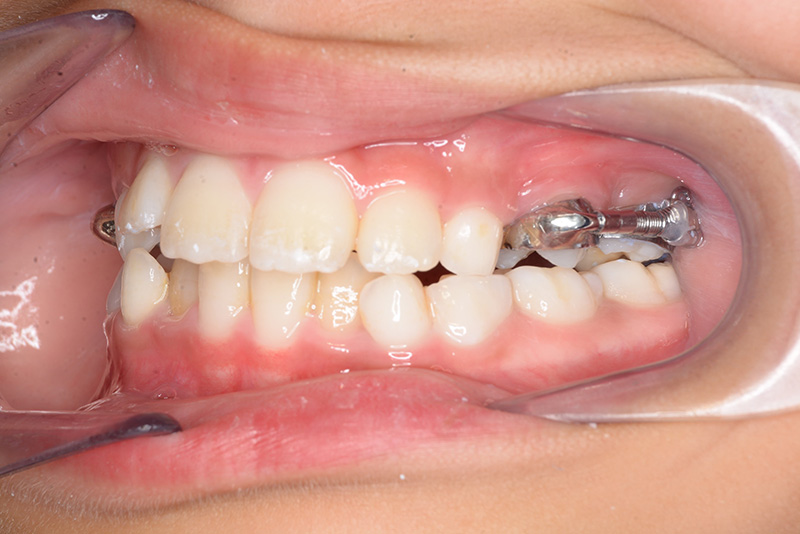

| 口腔内所見 | over jet 2.5mm、over bite 2.0mm、右側大臼歯関係はEnd on class Ⅱ、上顎左側Eは早期喪失により左側大臼歯関係はFull classⅡ、右側Eは6の異所萌出により歯根吸収が進行したため一般歯科医院にて抜去済みであった。 |

| パノラマ所見 | 上顎両側6、特に左側6は近心傾斜が認められ、両側5の萌出スペース不足が認められた。 |

| 批評・予后 | 早期に6の遠心移動を行いナンスのホールディングアーチにて保隙をした結果、5は良好な状態で萌出できたように思う。 今後は永久歯列完成まで経過観察を行っていく予定である。 |